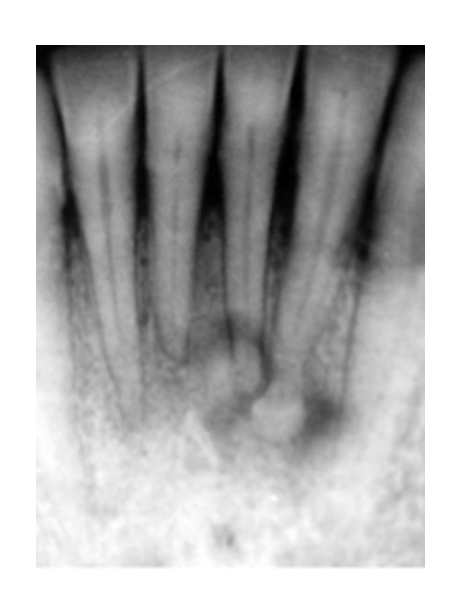

Periapical Cemento-Osseous Dysplasia (PCOD)

Reactive Process

* Unknown Origin

Most common:

* apices of mandibular anteriors

* Middled aged black females

* Vital Teeth

Starts RL–>progress to RO (w/RL halo) as it matures